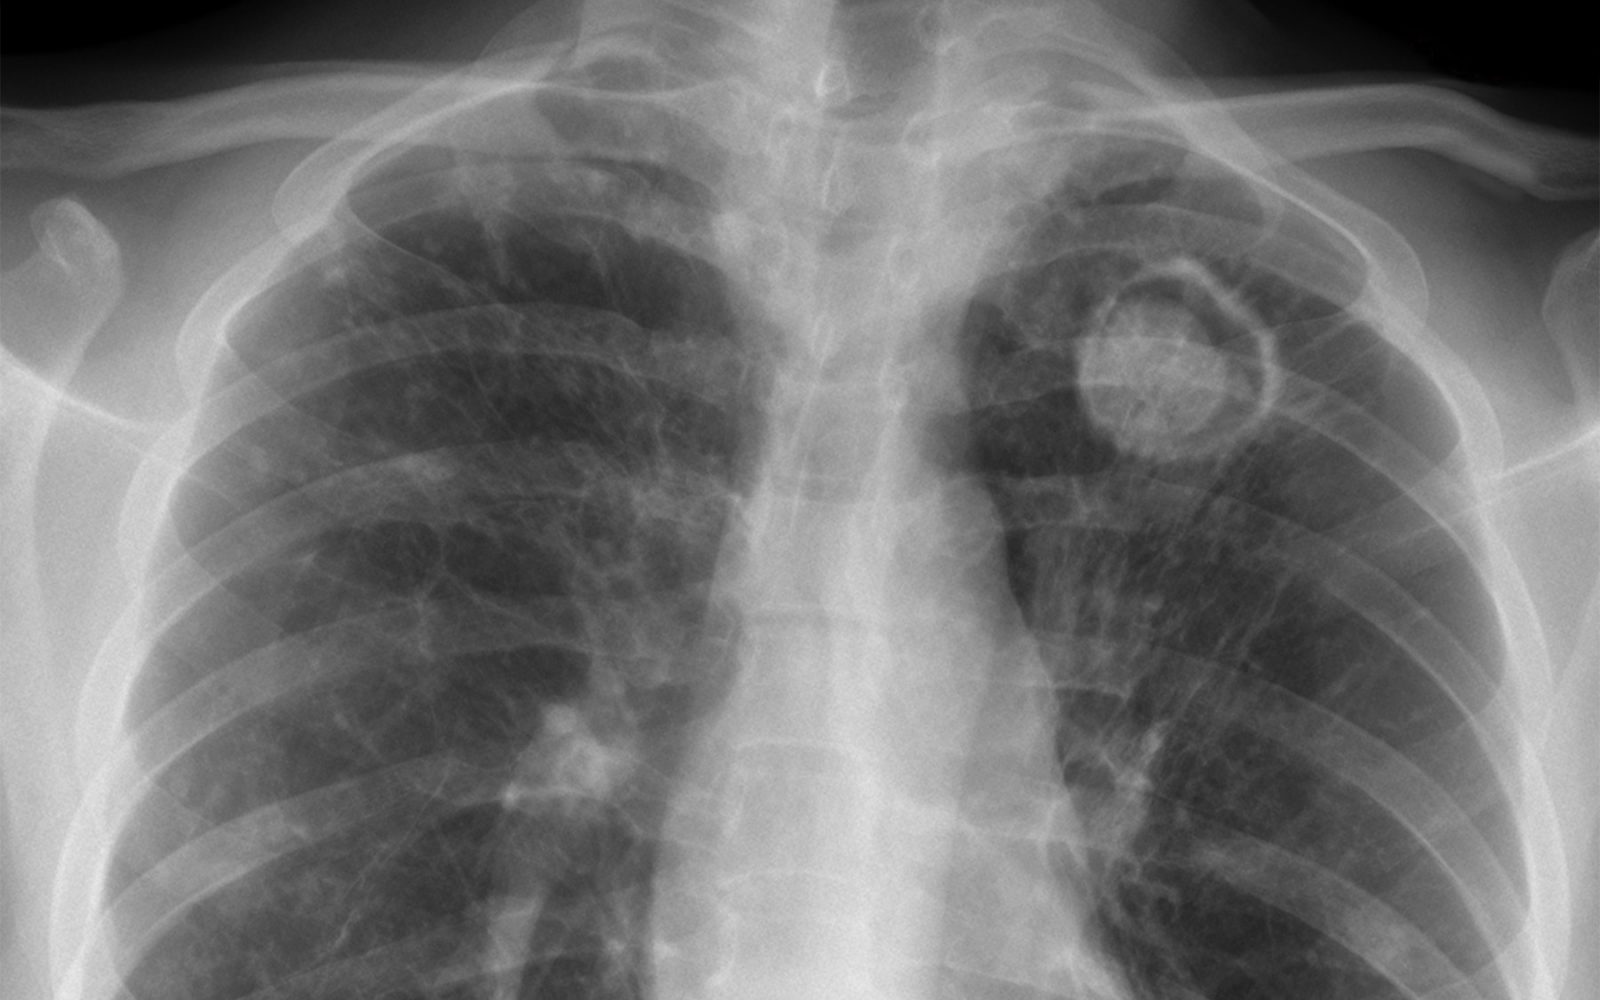

- lahko pri vdihavanju spor povzroči aspergilozo, resno pljučno bolezen, ki se lahko razširi tudi na možgane, srce in druge organe,

Aspergiloza se najpogosteje razvije v pljučih in se kaže s simptomi, ki so lahko sprva podobni običajni okužbi dihal. Vključujejo:

- težko dihanje, občutek sape ali stiskanja v prsih,

- vztrajen ali suh kašelj, včasih tudi z izmečkom ali sledmi krvi,

- povišano telesno temperaturo, zlasti če traja več dni brez jasnega vzroka,

- kronično utrujenost in splošno slabše počutje.

Pri hujših oblikah bolezni se gliva lahko razširi tudi izven pljuč, kar lahko povzroči resne zaplete, vključno z okužbo možganov, srca ali ledvic.